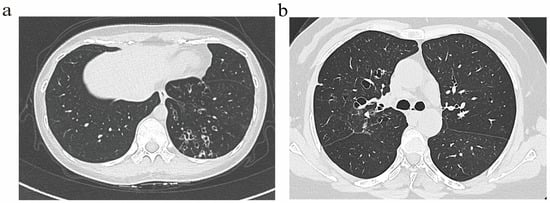

Bronchiectasis assessment followed BTS guidelines [14], excluding traction bronchiectasis. Imaging scoring referenced the Bhalla score [15]. Based on the generation of bronchial involvement demonstrated through HRCT, patients were classified into two radiological phenotypes: (1) The distal airway (DA) group (Figure 1a), defined by dilatation of the distal airway (the sixth generation and beyond). (2) The proximal–intermediate airway (PIA) group (Figure 1b), defined by dilatation of the proximal to intermediate airway (first to fifth generations). If a patient exhibited features of both proximal–intermediate and distal airway phenotypes, classification is determined based on the primary location, extent, and lobar distribution of structural abnormalities on HRCT. In this study, the (25-Bhalla score) was used instead of the total score of lung CT manifestations. For ease of writing, all references to the (25-Bhalla score) below are replaced by the Bhalla score. All images were evaluated by two respiratory physicians and one radiologist independently, who were blinded to the clinical information of patients. Discrepancies were resolved through consensus.

Figure 1.

Representative HRCT images illustrating distinct airway phenotype. (a) DA phenotype. (b) PIA phenotype.